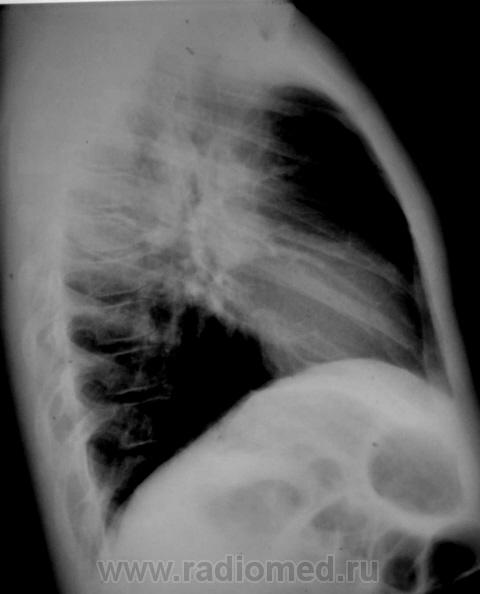

Девочка 10 лет. В течении трех недель беспокоит кашель, насморк, температуры не было, контакт с ОРВИ по дому. На 7.09.10 в легких выслушиваются разнокалиберные хрипы по всем полям,кашель, насморк. За весь период болезни получила симптоматическую терапию (климбутерол, виброцил, зиртек, эреспал, грудной сбор, физиотерапия). В ОАМ и ОАК без изменений.

Спасибо за улучшение качества снимков! Все может быть. Но уж больно смущают корни, особенно в боковой проекции

Мне тоже кажется, что корни расширены. Бронхоаденит тут не исключить. Требует дальнейшего обследования, оптимально - КТ груди с внутривенным контрастированием, для лучшей визуализации структур средостения. При отсутствии возможности - линейные томограммы.

Да, и томография нужна, да, и консультация фтизиатра не лишней будет.